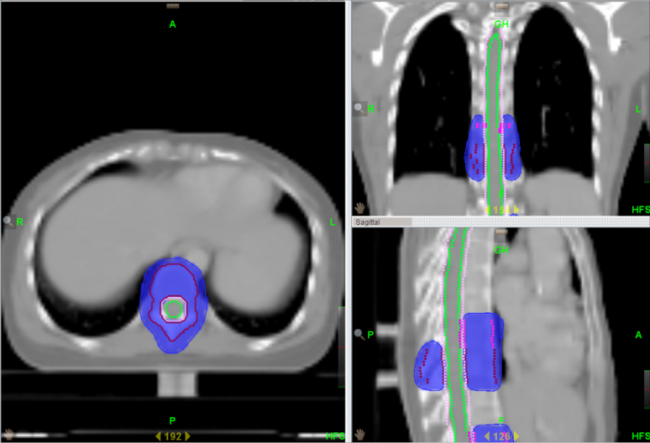

为了让“我”的优点发挥的更加明显,让更多的患者能够在“我”的治疗下得到痊愈。湘南学院附属医院引进的TomoTherapy(简称TOMO)——螺旋断层放疗系统,属于最新一代放射治疗设备。是目前唯一采用放疗照射与CT同源的影像引导放疗系统。成像精度高达±0.1mm,远远高于常规加速器。

与普通的“我”相比,TOMO放疗有以下优势:

1、对全身多发病灶及病变较长的大肿瘤,超出普通加速器治疗所能达到的范围,常规放疗往往不能同时包括,TOMO能够实现连续同时完成照射。包括易通过淋巴转移产生多病灶的恶性肿瘤、全脑全脊髓和全身骨髓调强照射等。

2、对解剖结构复杂等难治性、特殊的恶性肿瘤更具优势。包括鼻咽部肿瘤、全颅骨放疗、头皮恶性肿瘤、胸壁恶性肿瘤等。

3、对紧邻重要脏器或组织的恶性肿瘤,如肿瘤紧邻肝、肾、肺、鼻咽、前列腺等重要器官时,由于这些脏器对射线敏感,往往制约常规放疗放射剂量的提高,TOMO能够避开重要器官,降低副反应的同时提高放射剂量,使得既往不易放疗的患者变为可以放疗。